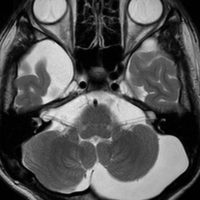

生後7カ月の幼児です。目が揺れるようになり(振り子様眼振)眼科を受診して腫瘍が発見されました。小児脳腫瘍の治療ができる病院へと紹介されました。

1ヶ月後にまたMRI検査がされました。乳児ですから検査にも麻酔が必要です。腫瘍は明らかに大きくなっています。左視神経から視索の腫瘍化が著しいので右側だけかすかに視力が残っているかもしれません。視力は明かりがわかる程度(明暗弁)と評価されました。